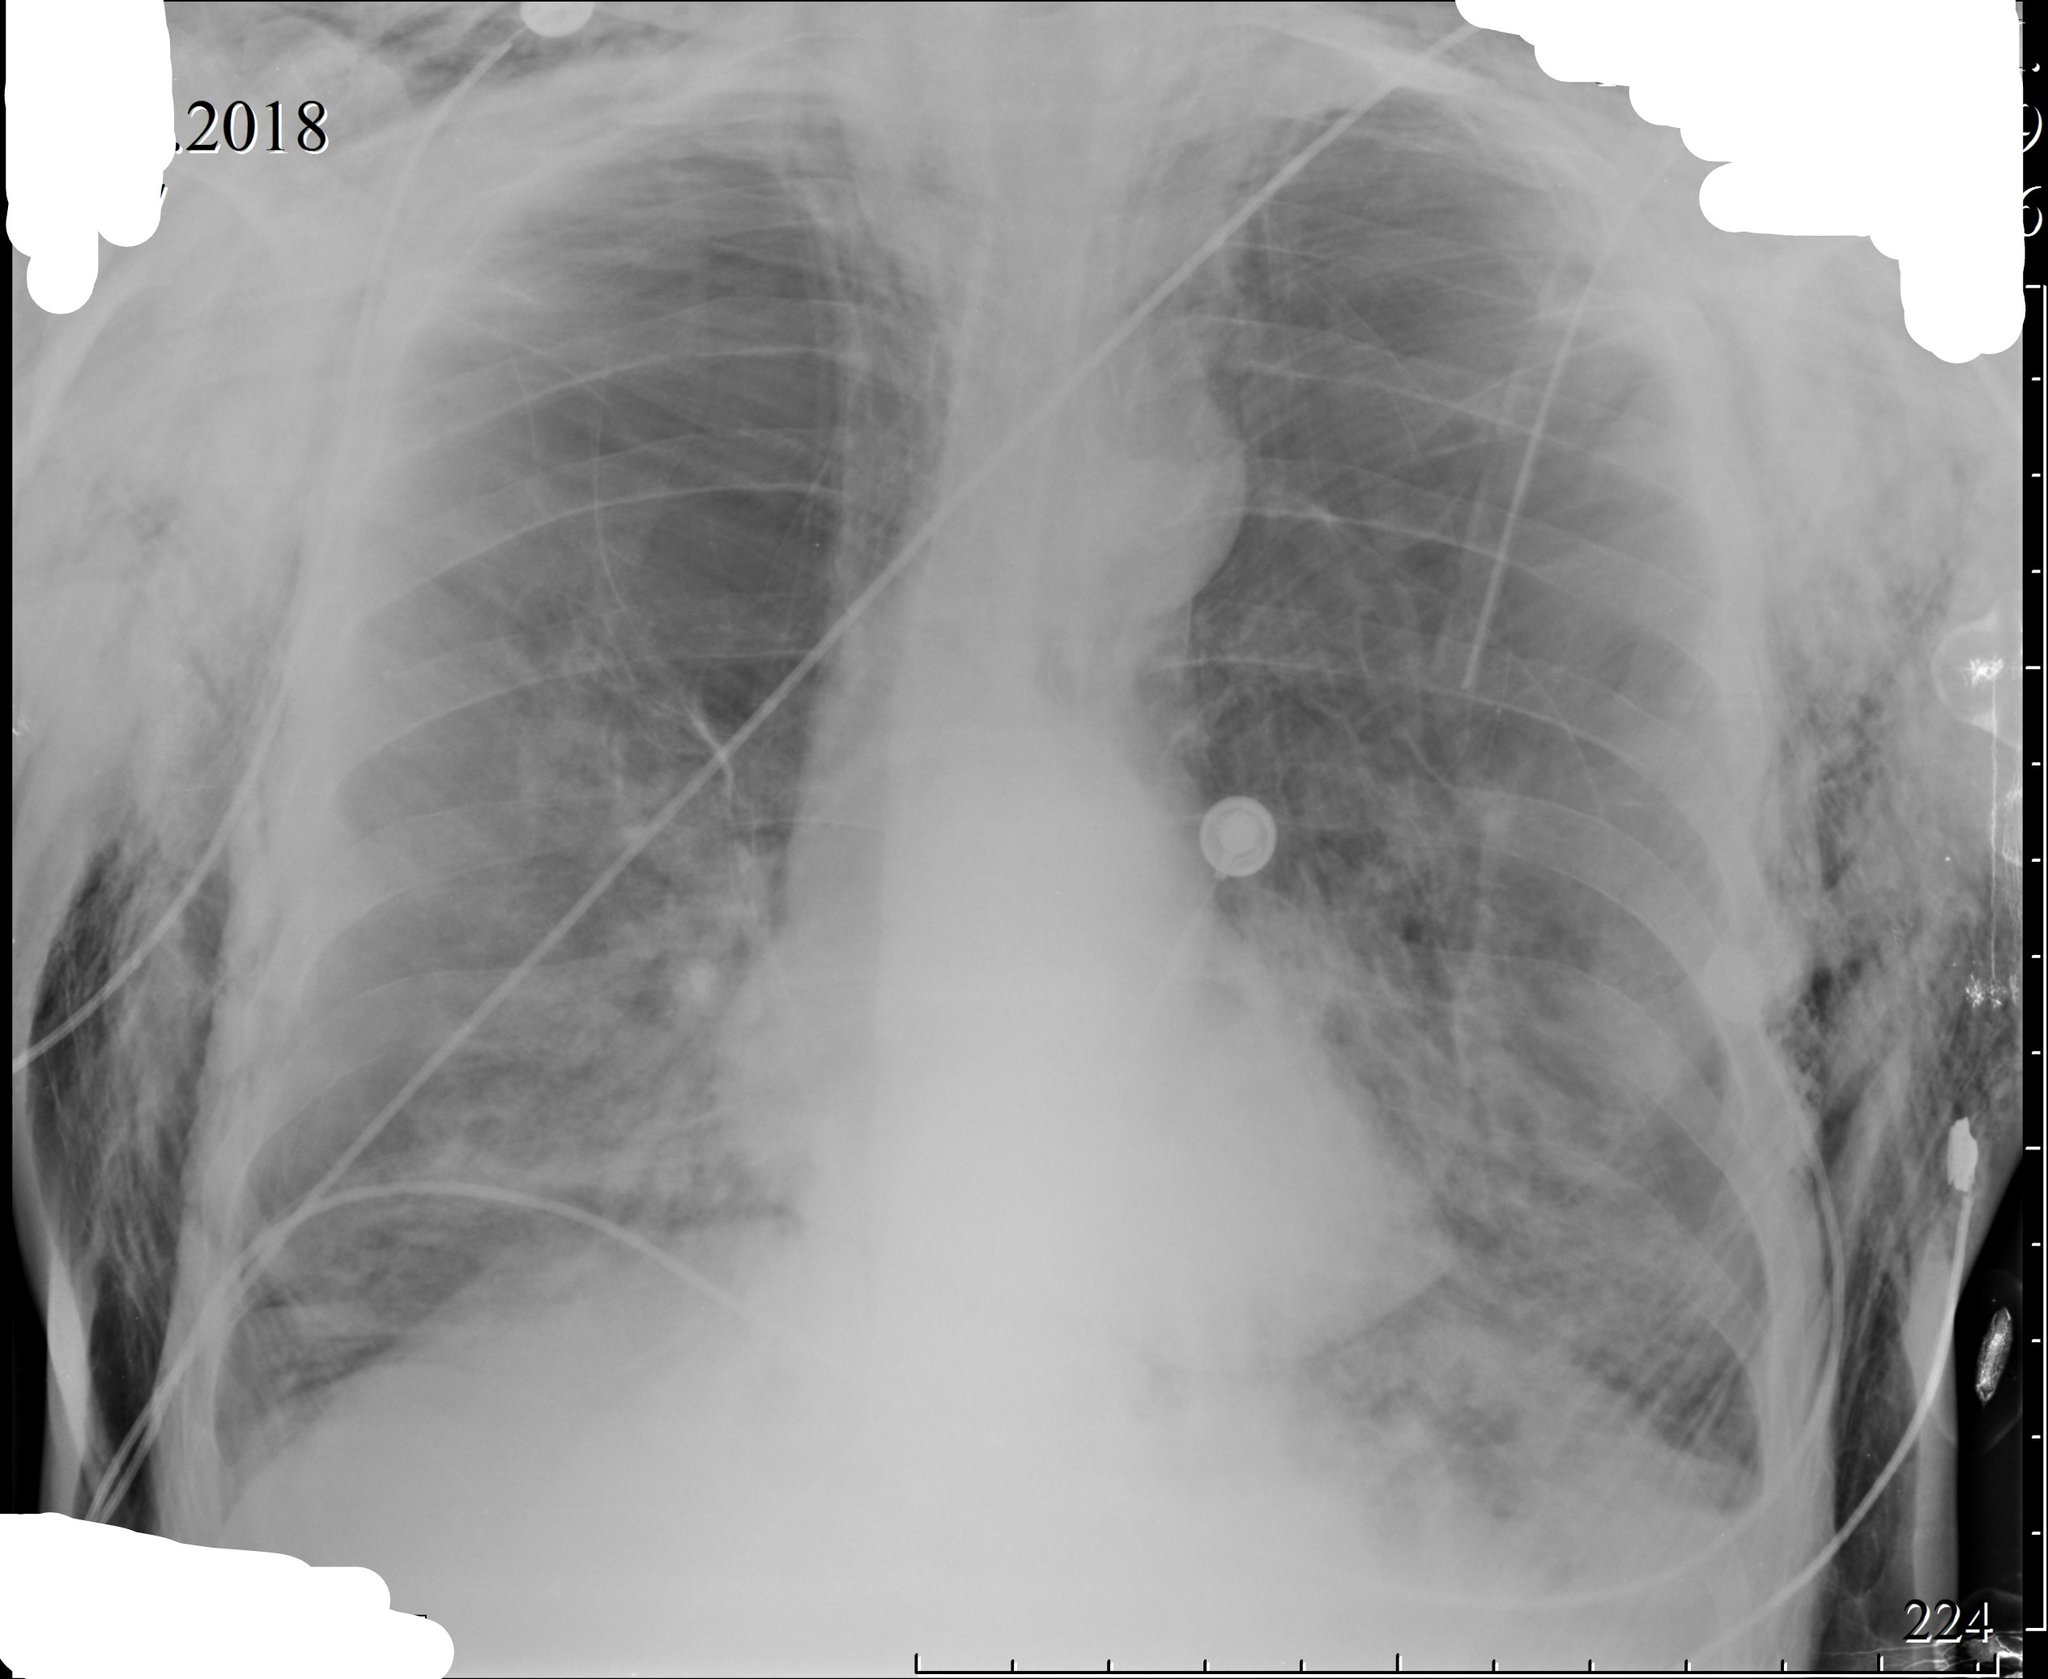

Фото рентгеновских снимков поражения легких при COVID-19

На фотографиях рентгеновских снимков видно, как вирус воздействует на легочную ткань. Характерные признаки поражения легких включают пятна, инфильтраты и наличие жидкости внутри легочных альвеол.

Фото рентгеновских снимков помогают врачам и специалистам визуально определить степень поражения легких и принять соответствующие меры лечения и поддержки пациента.